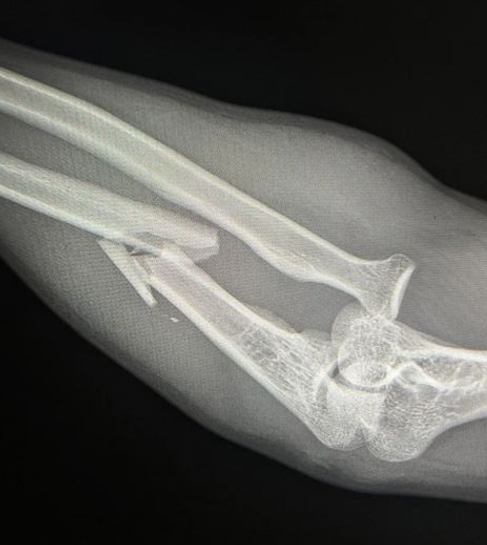

Recurrent instability

Complex proximal ulna fracture with radial head replacement subluxation